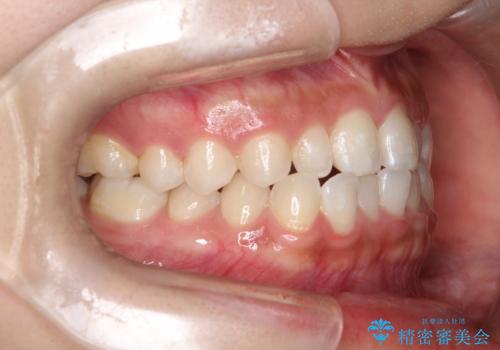

- 前歯の凸凹を主訴に来院された患者様です。

カウンセリング時に、側切歯が矮小歯であることを指摘したところ、適切な幅径での修復を希望されました。

インビザラインを用い、計画通りに歯並びを改善することができました。

矮小歯の幅径を大きくすることで、より理想的な噛み合わせを作ることができます。